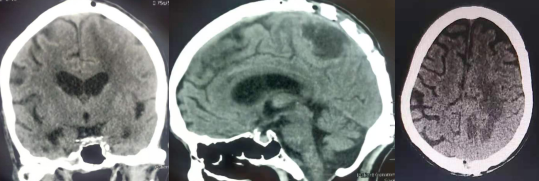

手术后CT影像(肿瘤已经切除)

开颅手术于2021年04月20日由神经外科王宏主任医师团队,贾杉副主任医师、麻醉医师及手术室护士的密切配合下,在显微镜下将肿瘤连同囊肿一并切除。术后中西医结合,加速康复治疗,患者偏瘫的右侧肢体功能很快恢复,出院时可搀扶下地行走,家属对科室工作人员给予了肯定并赠送锦旗表示感谢。出院后随访1月,目前患者右侧肢体肌力及感觉完全恢复正常,生活自理。